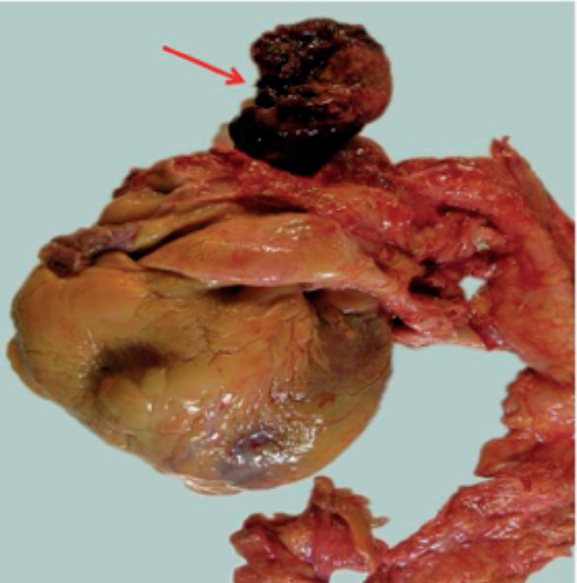

Given the presence of complete atrioventricular block and severe hypotension, in our case we considered implanting the Impella CP device (AbioMed, Danvers, Massachusetts, United States), which was the device that provided the highest utility since it does not require arterial pulse or an electrocardiographic registry to operate; however, performing a transthoracic echocardiography prior to the implantation of the device could have been decisive for diagnostic purposes and to re-think what was the best therapeutic strategy to use since, probably, the clinical situation of the patient was not only due to the STEMI, but also to the obstructive effect of the mass and the systemic embolization that may have exacerbated after the implantation of the device.